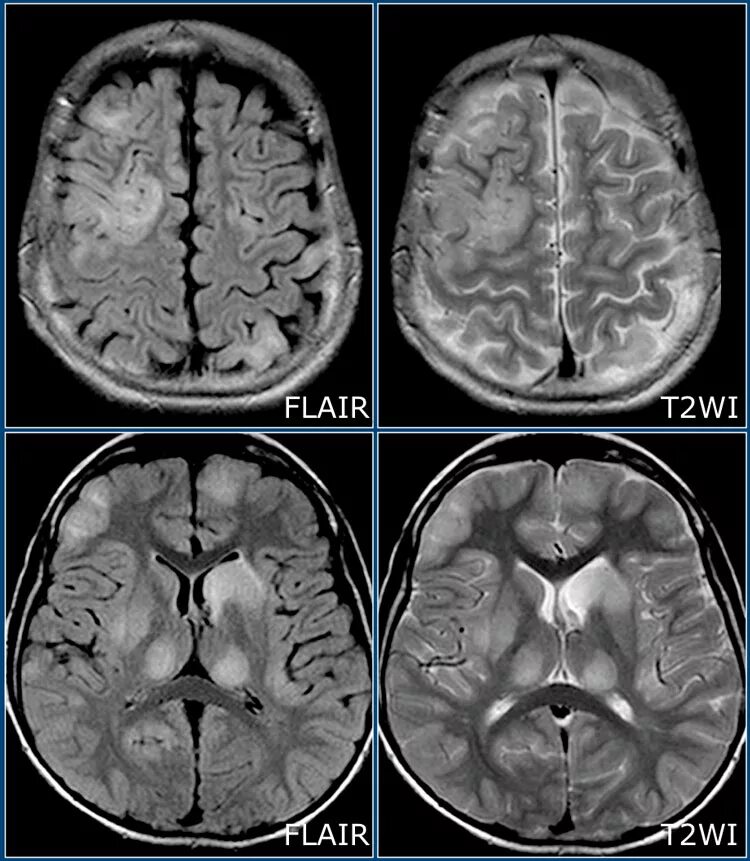

Мрт при каких заболеваниях